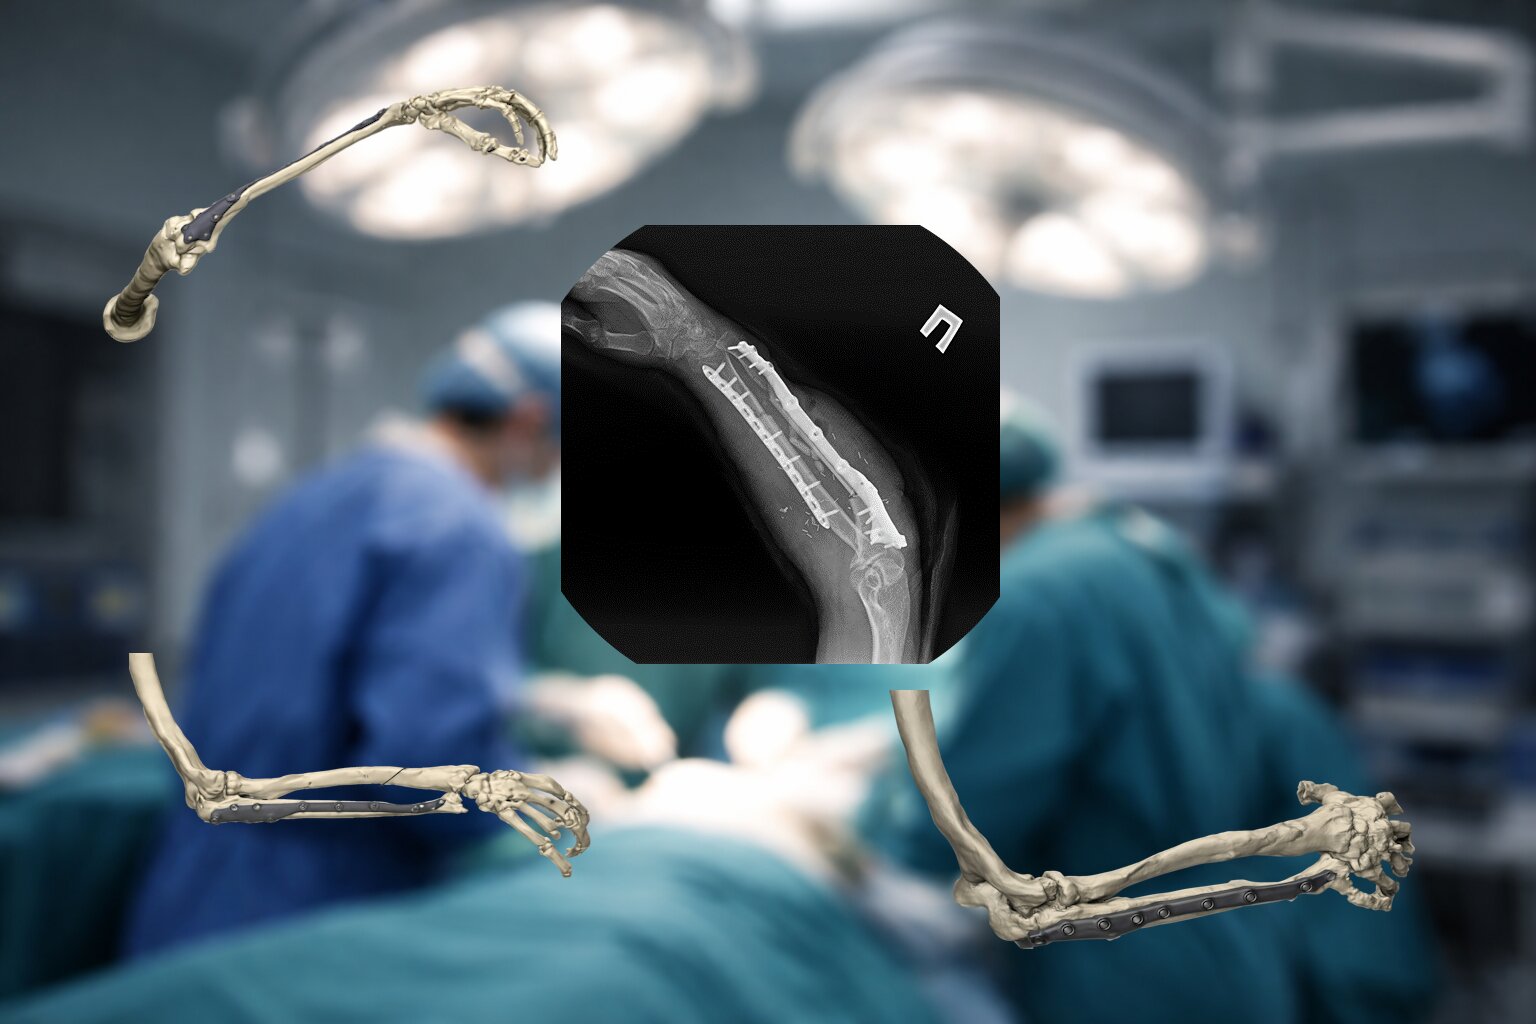

В связи с наличием рубцовой деформации и дефицита мягких тканей правого предплечья, дефекта правой локтевой кости до 10 см, было принято решение о проведении оперативного лечения в объеме пластики дефекта мягких тканей и локтевой кости свободным малоберцовым трансплантатом с фиксацией индивидуальной 3D-пластиной, металлоостеосинтеза лучевой кости правого предплечья пластиной. В рамках предоперационного планирования пациенту была выполнена компьютерная томография, на основе которой создан макет индивидуальной конструкции (рисунок 2).

На 95 сутки после ранения проведена реконструктивно-пластическая операция: пластика дефекта мягких тканей и локтевой кости правого предплечья свободным кожно-фасциально-костным малоберцовым лоскутом с фиксацией индивидуальной 3D пластиной, металлоостеосинтез лучевой кости правого предплечья пластиной.

Одним из оптимальных методов замещения огнестрельного диафизарного дефекта более 10 см, безусловно, является свободный кровоснабжаемый малоберцовый трансплантат. Индивидуальные пластины, изготовленные при помощи аддитивных технологий (3D-печать), позволяют точно адаптировать конструкцию к анатомии дефекта и трансплантата, обеспечивая стабильную фиксацию и снижая риск стрессовых переломов трансплантата. Таким образом, совмещение свободного малоберцового лоскута и индивидуальных пластин, изготовленных с помощью аддитивных технологий, является современным стандартом при реконструкции огнестрельных дефектов длинных трубчатых костей, обеспечивая высокую прочность фиксации, ускорение консолидации и снижение частоты осложнений.